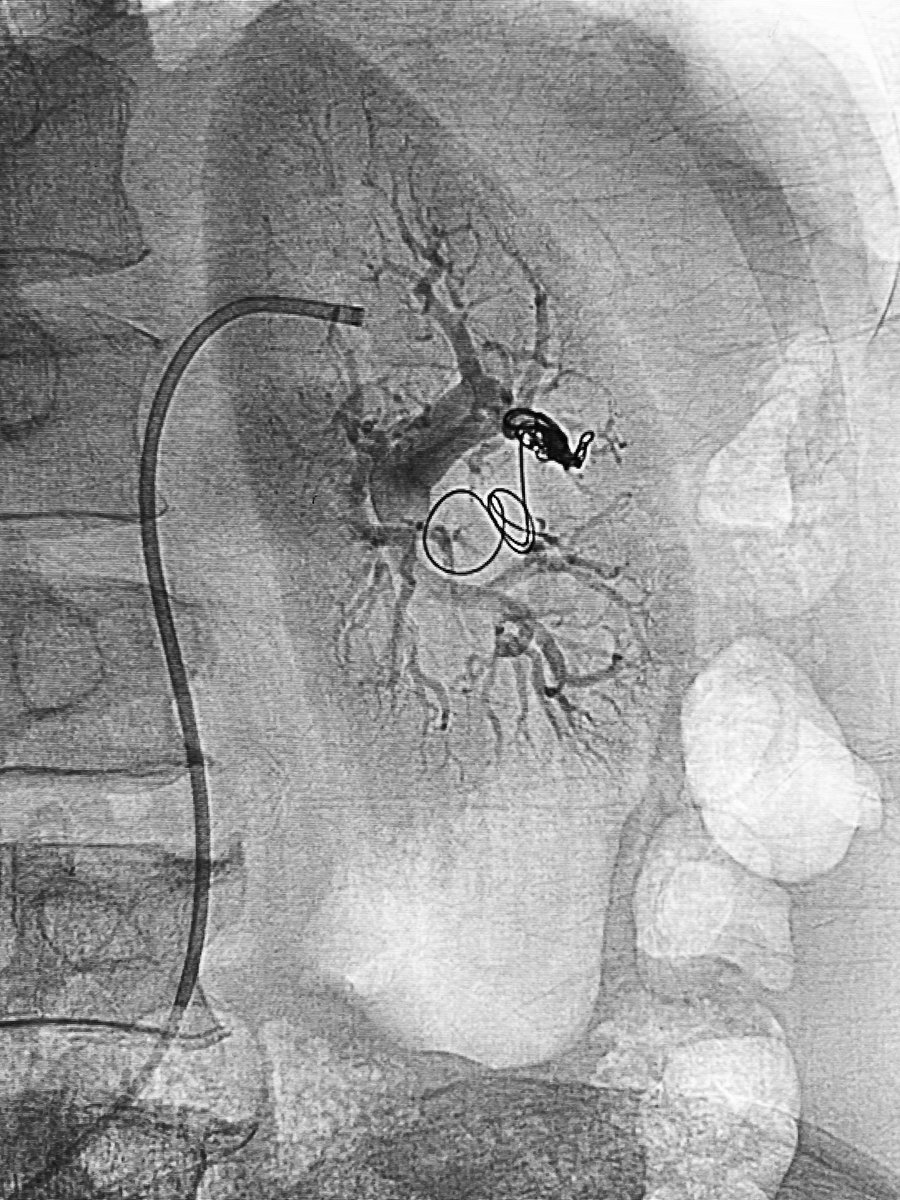

Type D2 CCF, closed by ipsilateral transvenous double-catheter technique for coiling and onyx injection. Minimal approach for better results :))